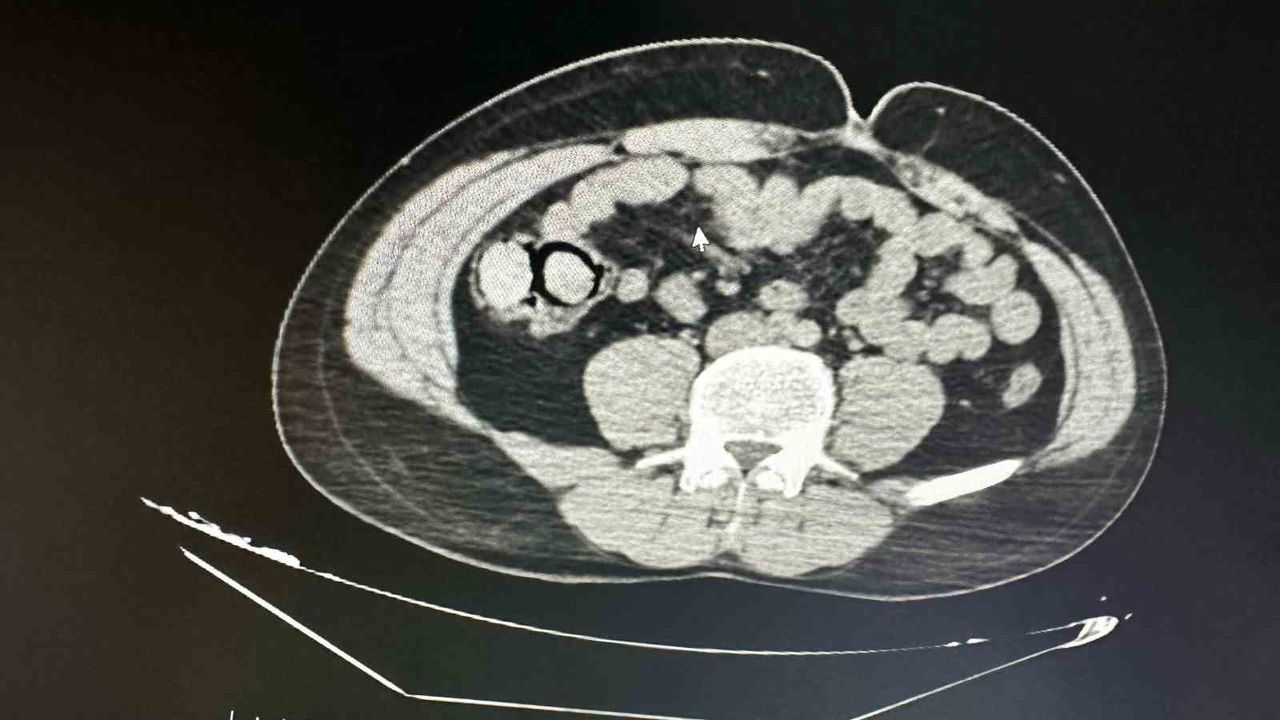

Bingöl Emniyet Müdürlüğü Narkotik Suçlarla Mücadele Şube Müdürlüğüne bağlı narko-timleri akıllara durgunluk veren bir uyuşturucu kaçakçılığını çözdü. Ekiplerin çalışmaları neticesinde otobüs ile Bingöl’e gelen şüpheli yabancı uyruklu 2 şahsın iç beden muayenesinde 10 parça halinde 113 gram metamfetamin maddesi tespit edildi. Emniyetteki işlemlerinin ardından mahkemeye çıkarılan 2 şahıs, uyuşturucu madde ticareti yapmak suçundan tutuklanarak Elazığ Kapalı ceza infaz kurumuna teslim edildi.